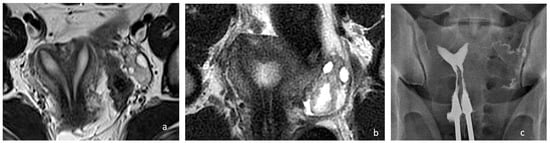

A single uterine cavity was obtained, as confirmed by MRI (Figure 2).

Figure 2. Preoperative and postoperative examination of case 1. (a) MRI T2, WI, confirmed the presence of a Müllerian anomaly and identified it as a complete septate uterus, duplicated cervix, and longitudinal vaginal septum (Class U2bC2V1 of the ESHRE/ESGE classification). Additionally, it provided information regarding the septum’s thickness, which measured 4–6 mm. (b) Postoperative MRI showing a uterine cavity. (c) Control hysterosalpingography performed 3 months after surgery, demonstrating a single uterine cavity.

The patient was discharged on the same day with a two-month estrogen pill regimen to prevent intrauterine adhesion formation. She reported no dyspareunia after the intervention.

The hysterosalpingography performed five months after surgery confirmed the presence of a single uterine cavity with an indentation of 10 mm at the fundus and a residual fundal thickness of 18 mm (Figure 2c). No intrauterine adhesions were found.